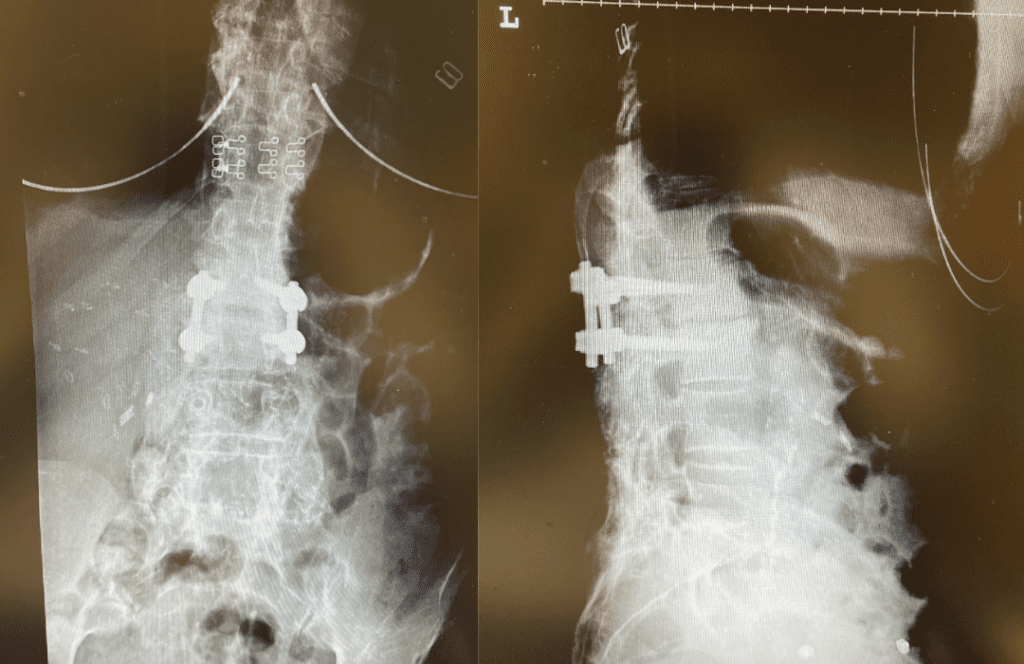

This 62-year-old female presents with chronic intractable low back pain with radiation down the front of her thighs. The patient had had two prior fusion surgeries: She initially had an L4-S1 fusion twelve years prior and a subsequent revision extension of her fusion at L3-4 that she had three years prior. She had a long-term history of smoking. She had mild hip flexor weakness, right greater than right. Imaging studies revealed next segment degeneration and stenosis at L2-3. (Figs. 1a and 1b and 2).

Figures 1a and 1b. Sagittal T2 MRIs of the lumbar spine demonstrating L2-3 stenosis after L3-4 instrumented fusion.